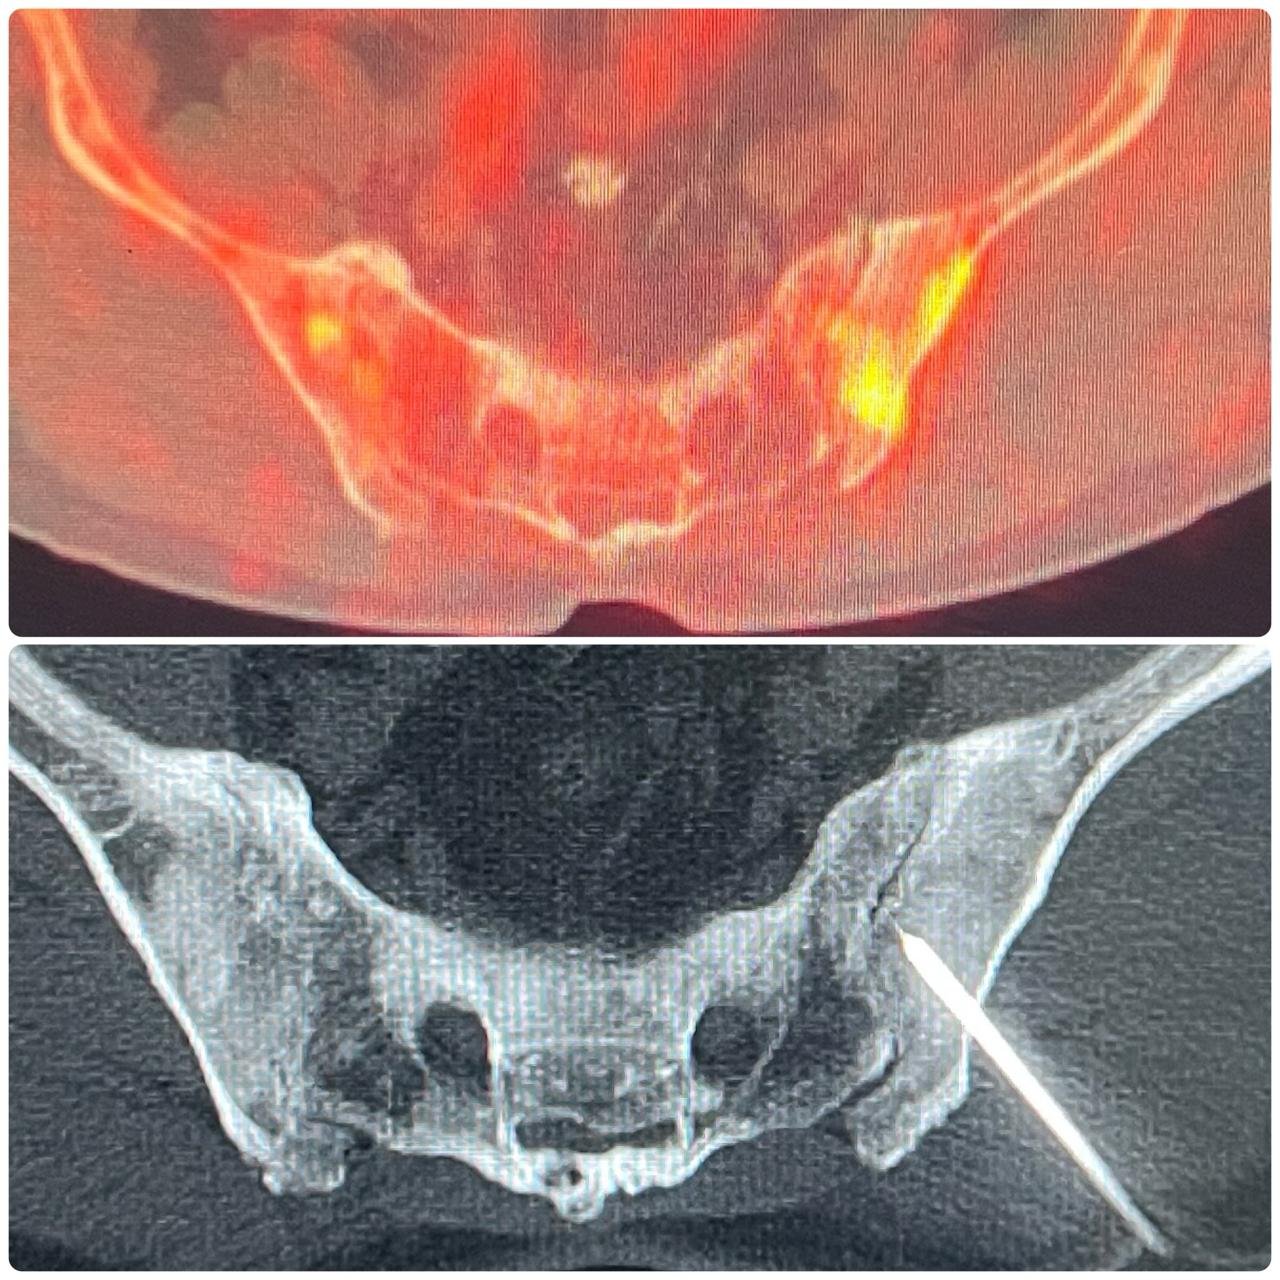

Oncological Interventions: TACE, TARE, Thermal Ablations, Liver Transplant Interventions

Neurovascular & Other Procedures: Osteoid Osteoma Ablations, Neurovascular Interventions